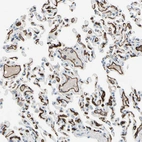

Immunohistochemistry analysis in human lung and skeletal muscle tissues using HPA009300 antibody. Corresponding CD93 RNA-seq data are presented for the same tissues.